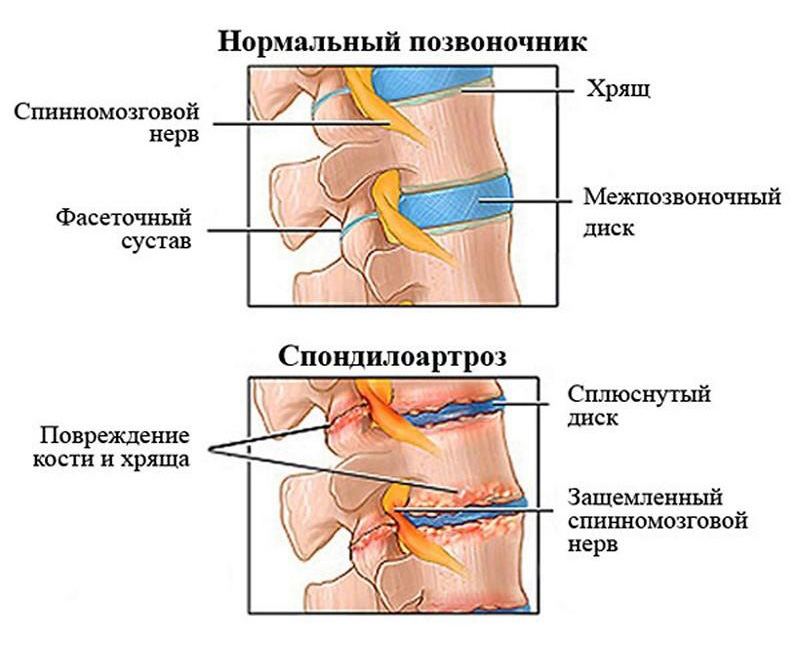

Остеоартрит фасеточных суставов: медицинские снимки и схемы